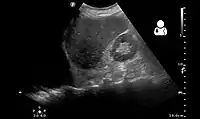

Ultrasonography may be used to detect hemothorax and other pleural effusions. This technique is of particular use in the critical care and trauma settings as it provides rapid, reliable results at the bedside.[23] Ultrasound is more sensitive than chest x-ray in detecting hemothorax.[25] Ultrasound can cause issues in people who are morbidly obese or have subcutaneous emphysema. When CT is unavailable in the current setting or the person cannot be moved to the scan, ultrasound is used.[3]

Ultrasound scan of the chest showing a left-sided hemothorax